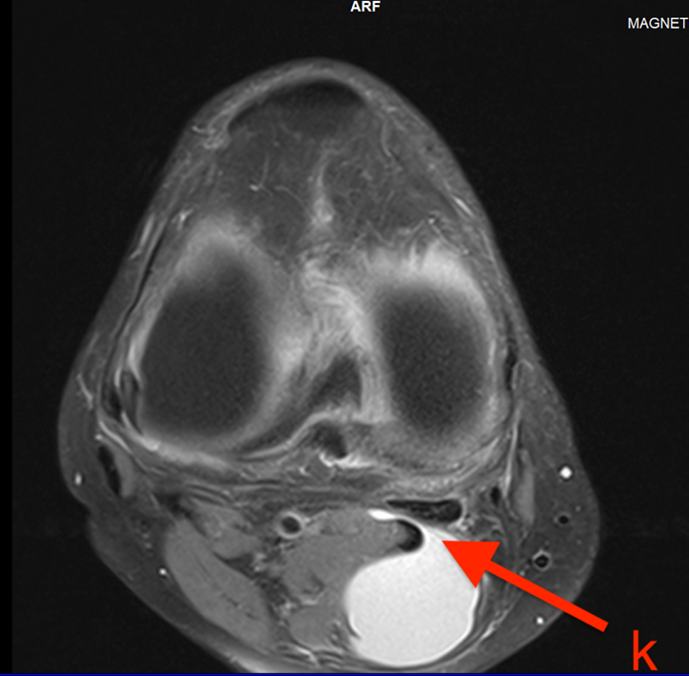

Rezonans magnetyczny cysty Bakera (MRI)

Rezonans magnetyczny nie tylko potwierdza obecność cysty, ale umożliwia dokładną ocenę współistniejących patologii wewnątrzstawowych10. W obrazach T2-zależnych cysta prezentuje się jako jednorodny obszar wysokiego sygnału położony w dole podkolanowym z charakterystycznym połączeniem ze stawem11. MRI jest szczególnie przydatne w planowaniu leczenia operacyjnego oraz w diagnostyce różnicowej, umożliwiając odróżnienie cysty od torbieli łąkotki, guzów, tętniaków czy krwiaków. Zdjęcia 1,2